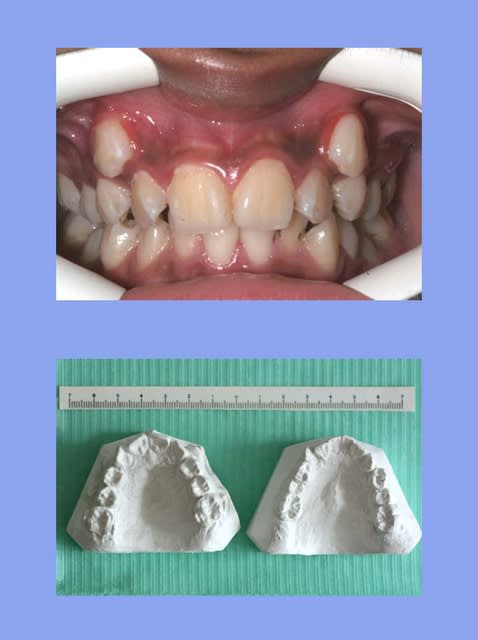

1 e3acmi - Eugenol

2 xg9czy - Eugenol

3 koixmk - Eugenol